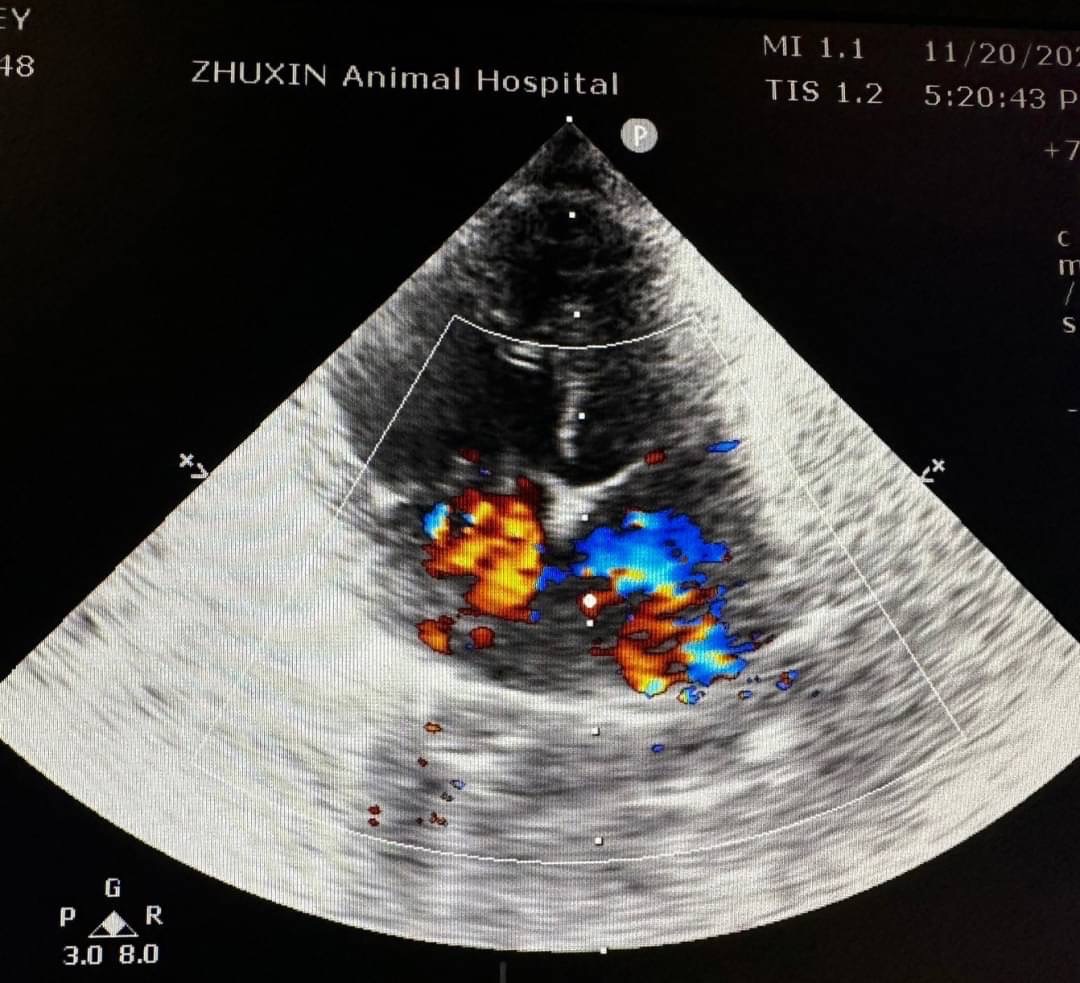

貓咪的心臟病

更多